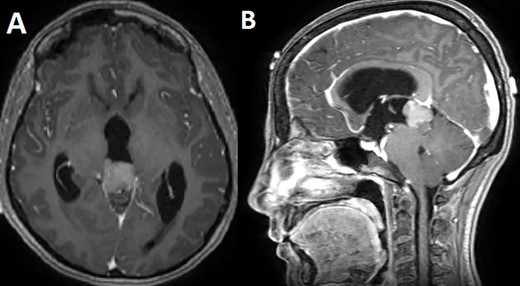

A 33-year-old lady presented to the clinic for bilateral retro-orbital headache with tinnitus most severe upon waking up in the morning for 3 months, without evidence of nausea, vomiting, or insomnia. Vital signs were within the normal range. The neurologic exam was non-focal. Enhanced brain magnetic resonance imaging (MRI) revealed a T1 hypointense, T2 hyperintense, homogenously enhancing Pineal tumor of 2 × 1.89 × 1.61 cm (anteroposterior × transverse × height) compressing the posterior wall of the third ventricle with evidence of moderate hydrocephalus (Fig. 1). The patient was scheduled for craniotomy for resection of the mass. In the operating room, an external ventricular drain was inserted in the right occipital horn followed by craniotomy and resection of the mass through a right occipital transtentorial approach. Gross total surgical resection was achieved under microscopic navigation (Fig. 2). The patient was extubated. Upon extubation the patient started to have chewing-like movement of her lips on the ET tube, afterward, she was transferred to the intensive care unit for monitoring. On postoperative day 1, we noticed that the patient was still having chewing-like movements typical of orofacial dyskinesia with evidence of buccal mucosal injury and swelling of the lips (Video 1). She was also complaining of inability to sleep. The patient was on regular postoperative medications (esomeprazole, cefazolin, paracetamol, morphine, dexamethasone, levetiracetam). An enhanced postoperative brain MRI was done for evaluation and confirmed complete resection of the lesion without any bleeding or ischemic changes (Fig. 3). The chewing like movements lasted for 72 hours and spontaneously resolved afterward. Pathology confirmed pineal parenchymal tumor of intermediate differentiation (WHO Grade III). The patient was treated with adjuvant radiotherapy. This is an unreported complication post pineal gland tumor resection in humans. Below we review the literature reporting abnormal facial movements associated with various pineal gland conditions as the data remains scarce concerning dyskinesia post pineal tumors resection in humans.

T1 enhanced axial (A) and sagittal (B) MRI showing a T1 hypointense homogenously enhancing pineal tumor.